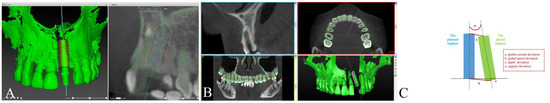

2.5. Accuracy Measurements